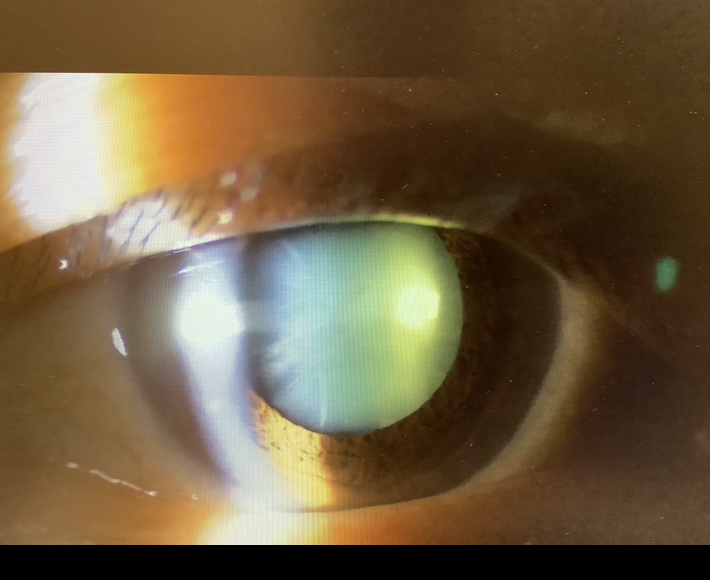

手術の申し込みは、白内障3人と眼瞼下垂1人、今日の手術は、眼瞼下垂3人、霰粒腫5人(2歳男の子2人、2歳女の子、6歳女の子、48歳女性)、眼瞼腫瘤切除1人でした。

今日、白内障の手術の申し込みをいただいた60代の女性の方は、12年前に原田病になり、昭和大学藤が丘病院に入院し、ステロイドパルスの点滴治療を受けたそうで、その時の担当医がなんと僕だったようです。確かに僕が藤が丘にいた時で、原田病の患者さんも何人か受け持っていて、なんとなく名前も記憶にあったので、きっと12年振りの再会で間違いないと思いました。